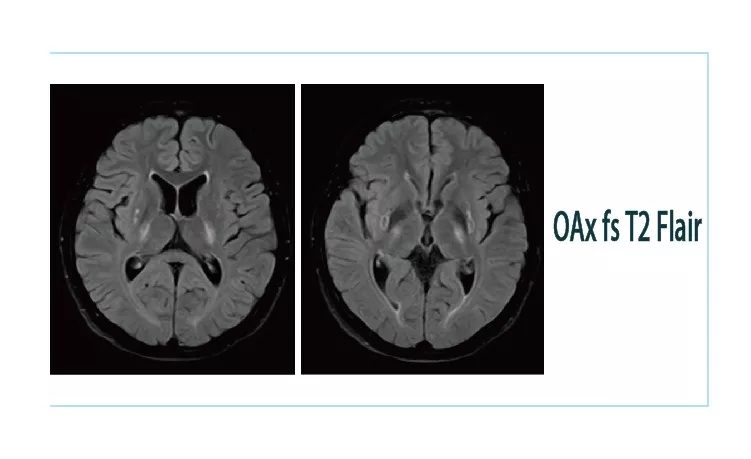

1544579634898245.jpg1544579646797662.jpg